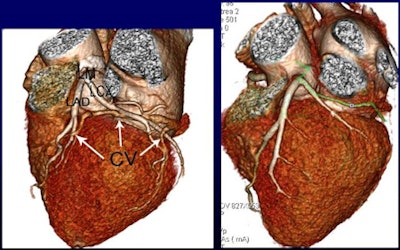

The researchers scanned more than 100 patients using contrast volumes of 0.8, 0.7, or 0.6 mL/kg, measuring CT attenuation in the ascending and descending aorta, left and right coronary arteries, and coronary sinus. CT values in the ascending and descending aorta and coronary arteries exceeded 300 HU in all three contrast groups.

The study team measured attenuation at regions of interest in the ascending and descending aorta, left and right coronary arteries, and coronary sinus.

CT values in the coronary sinus were 112.7, 93.7, and 81.2 HU for Groups A, B, and C, respectively (p < 0.001). CT values within the ascending and descending aorta and the coronary arteries were higher than 300 HU in all three contrast groups.

CCTA protocols limited to 0.6 mL/kg of contrast, with homogeneous enhancement in the coronary arteries, can be achieved using 640-slice volume CT, Zhong-Xiang concluded.